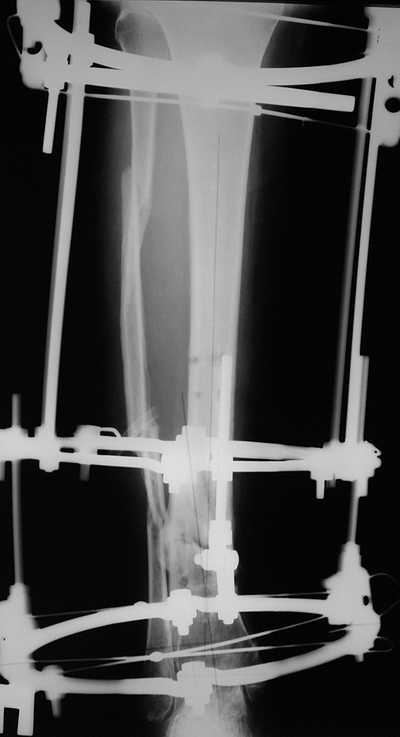

Male 54 years old, diabetic, blind in both eyes, with infected (MRSA) non union distal tibia after fracture 8 month ago. In acute phase treated by ORIF with LCP tibia and fibula. Treatment complicated by infection and after 6 month hardware was removed and treatment continued by cast fixation. You can see malposition of fragments In this stage beginning treated by Ilizarov fixation with use Hexapod system, allows anatomical position of fragments and you see signs of union.